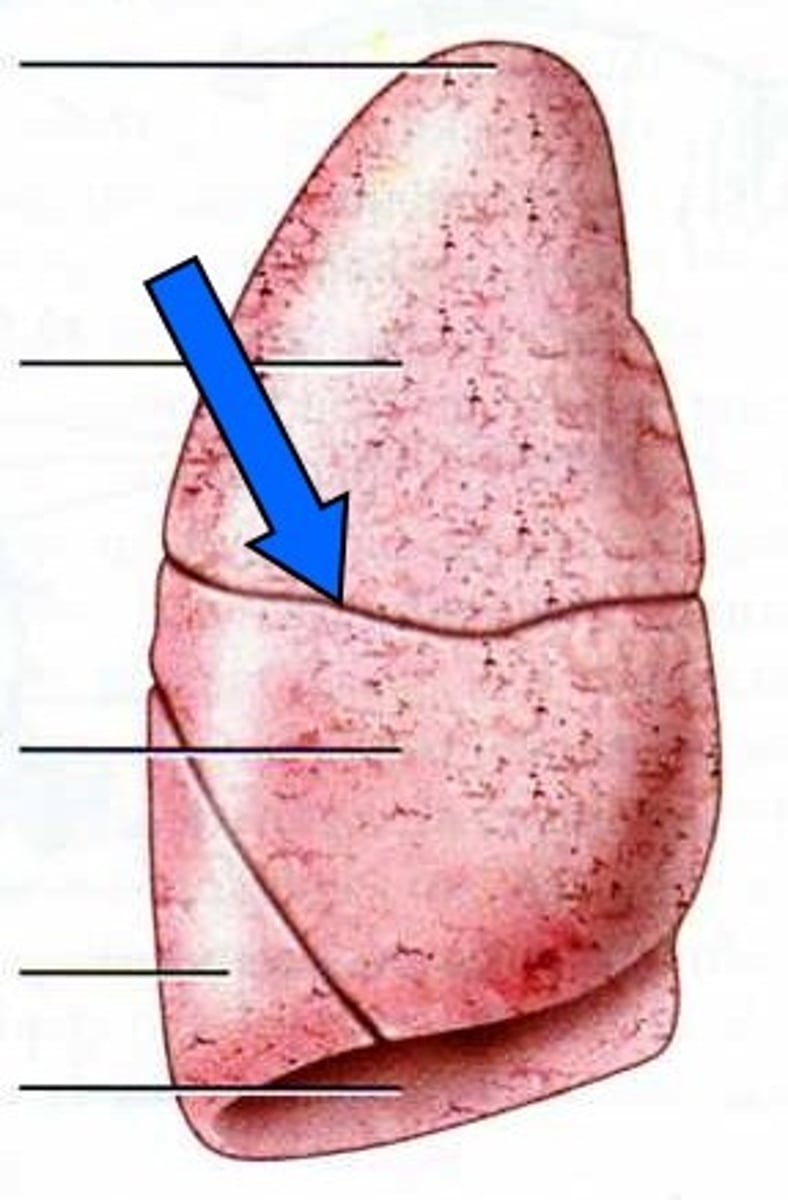

lobes

smaller units that compose each lung

fissure

separates lobes in each lung

horizontal fissure

separates the superior and middle lobes of the right lung

right oblique fissure

separates the right middle and inferior lobes

left oblique fissure